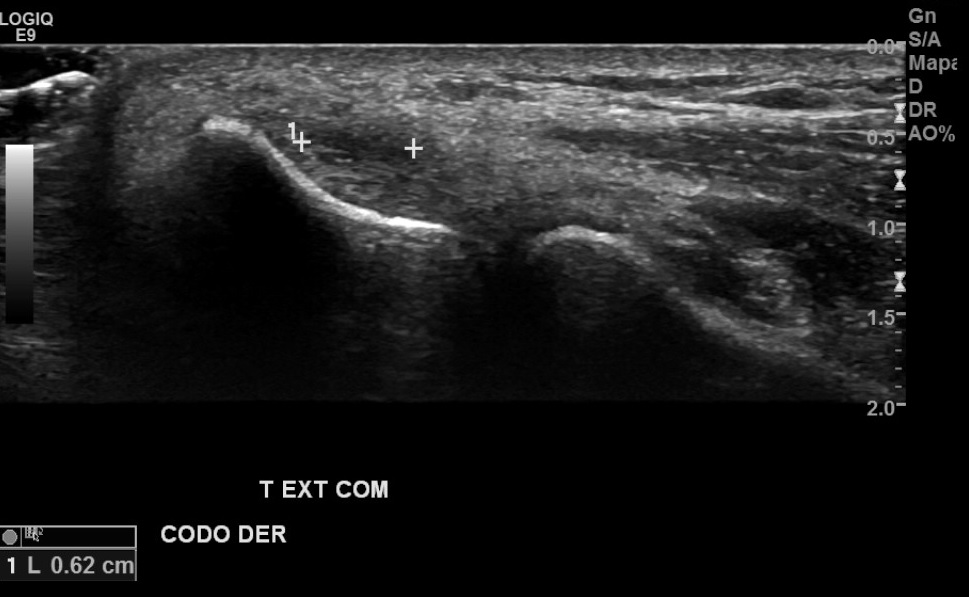

Antecedentes: dolor en región epicondilo lateral derecho de larga data, sin trauma, por exigencia laboral de EESS.

Hallazgos: Tendón extensor común de codo derecho se observa de parénquima marcadamente heterogéneo, con foco de desgarro de espesor y ancho parcial en su espesor, con escasa vascularización al doppler color.